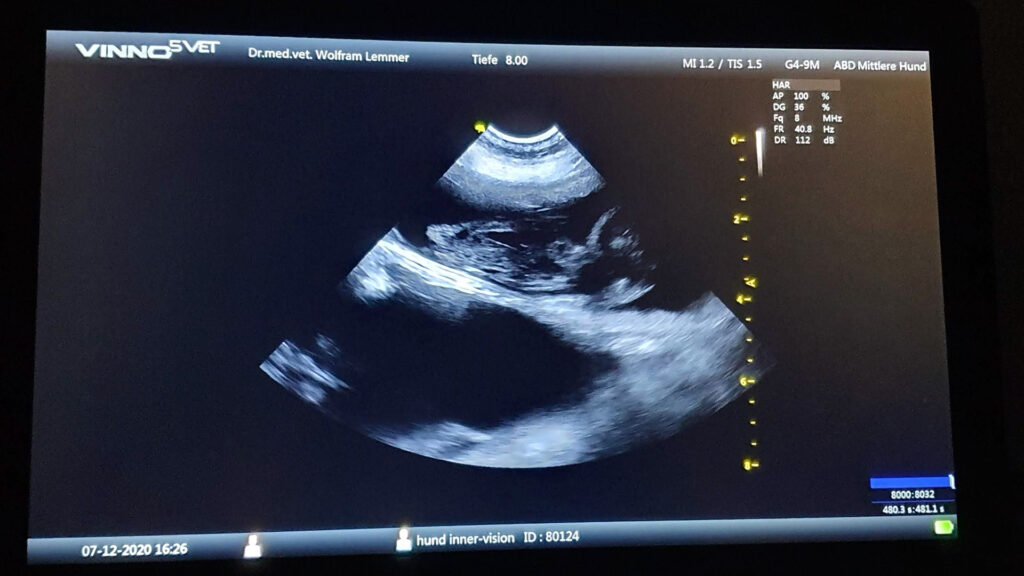

On December 7th, she was scanned in the vet clinic. The date was late, we wanted to be sure.

The fetusses were already quite big. The vet counted 5 to 6, and we were happy that Opra finally would have puppies.